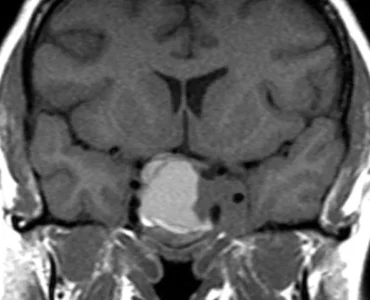

Advanced Pituitary Surgery: No Incision, Faster Recovery! 🧠✨ Jadeed technique se mehfooz aur mo`asar ilaaj.

Are you or a loved one dealing with vision issues, hormonal imbalances, or persistent headaches? 😰 These can often be signs of a pituitary tumor. Traditionally, brain surgery meant large incisions and long recovery times, but medical science has evolved.

At The Brain & Spine Centre, we offer Advanced Pituitary Surgery using the Transnasal Endoscopic approach. This means the tumor is reached through the nose—leaving no external scars, preserving your vision, and ensuring a much faster return to your normal life.

Why Choose Transnasal Endoscopic Surgery?

Minimally Invasive: No external incisions or scars.

Vision Preservation: Targeted approach to protect the optic nerves.

Hormonal Recovery: Helps restore normal body functions.

Faster Healing: Significantly reduced hospital stay and recovery time.

Don`t let a diagnosis overwhelm you. Trust our neuro experts to provide the most advanced, compassionate care available.